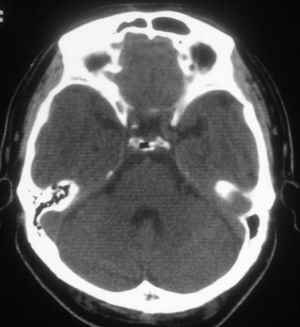

标题: CT20507:请问老师,鞍背正常吗??

空蝶鞍,正常变异

鞍背正常——为蝶窦过度气化所致。

是的,正常鞍区表现。鞍背骨质的低密度气体为蝶窦过度气化所致!

正常鞍区表现。鞍背骨质的低密度气体为蝶窦过度气化所致!

正常,鞍背骨质的低密度气体为蝶窦过度气化所致。